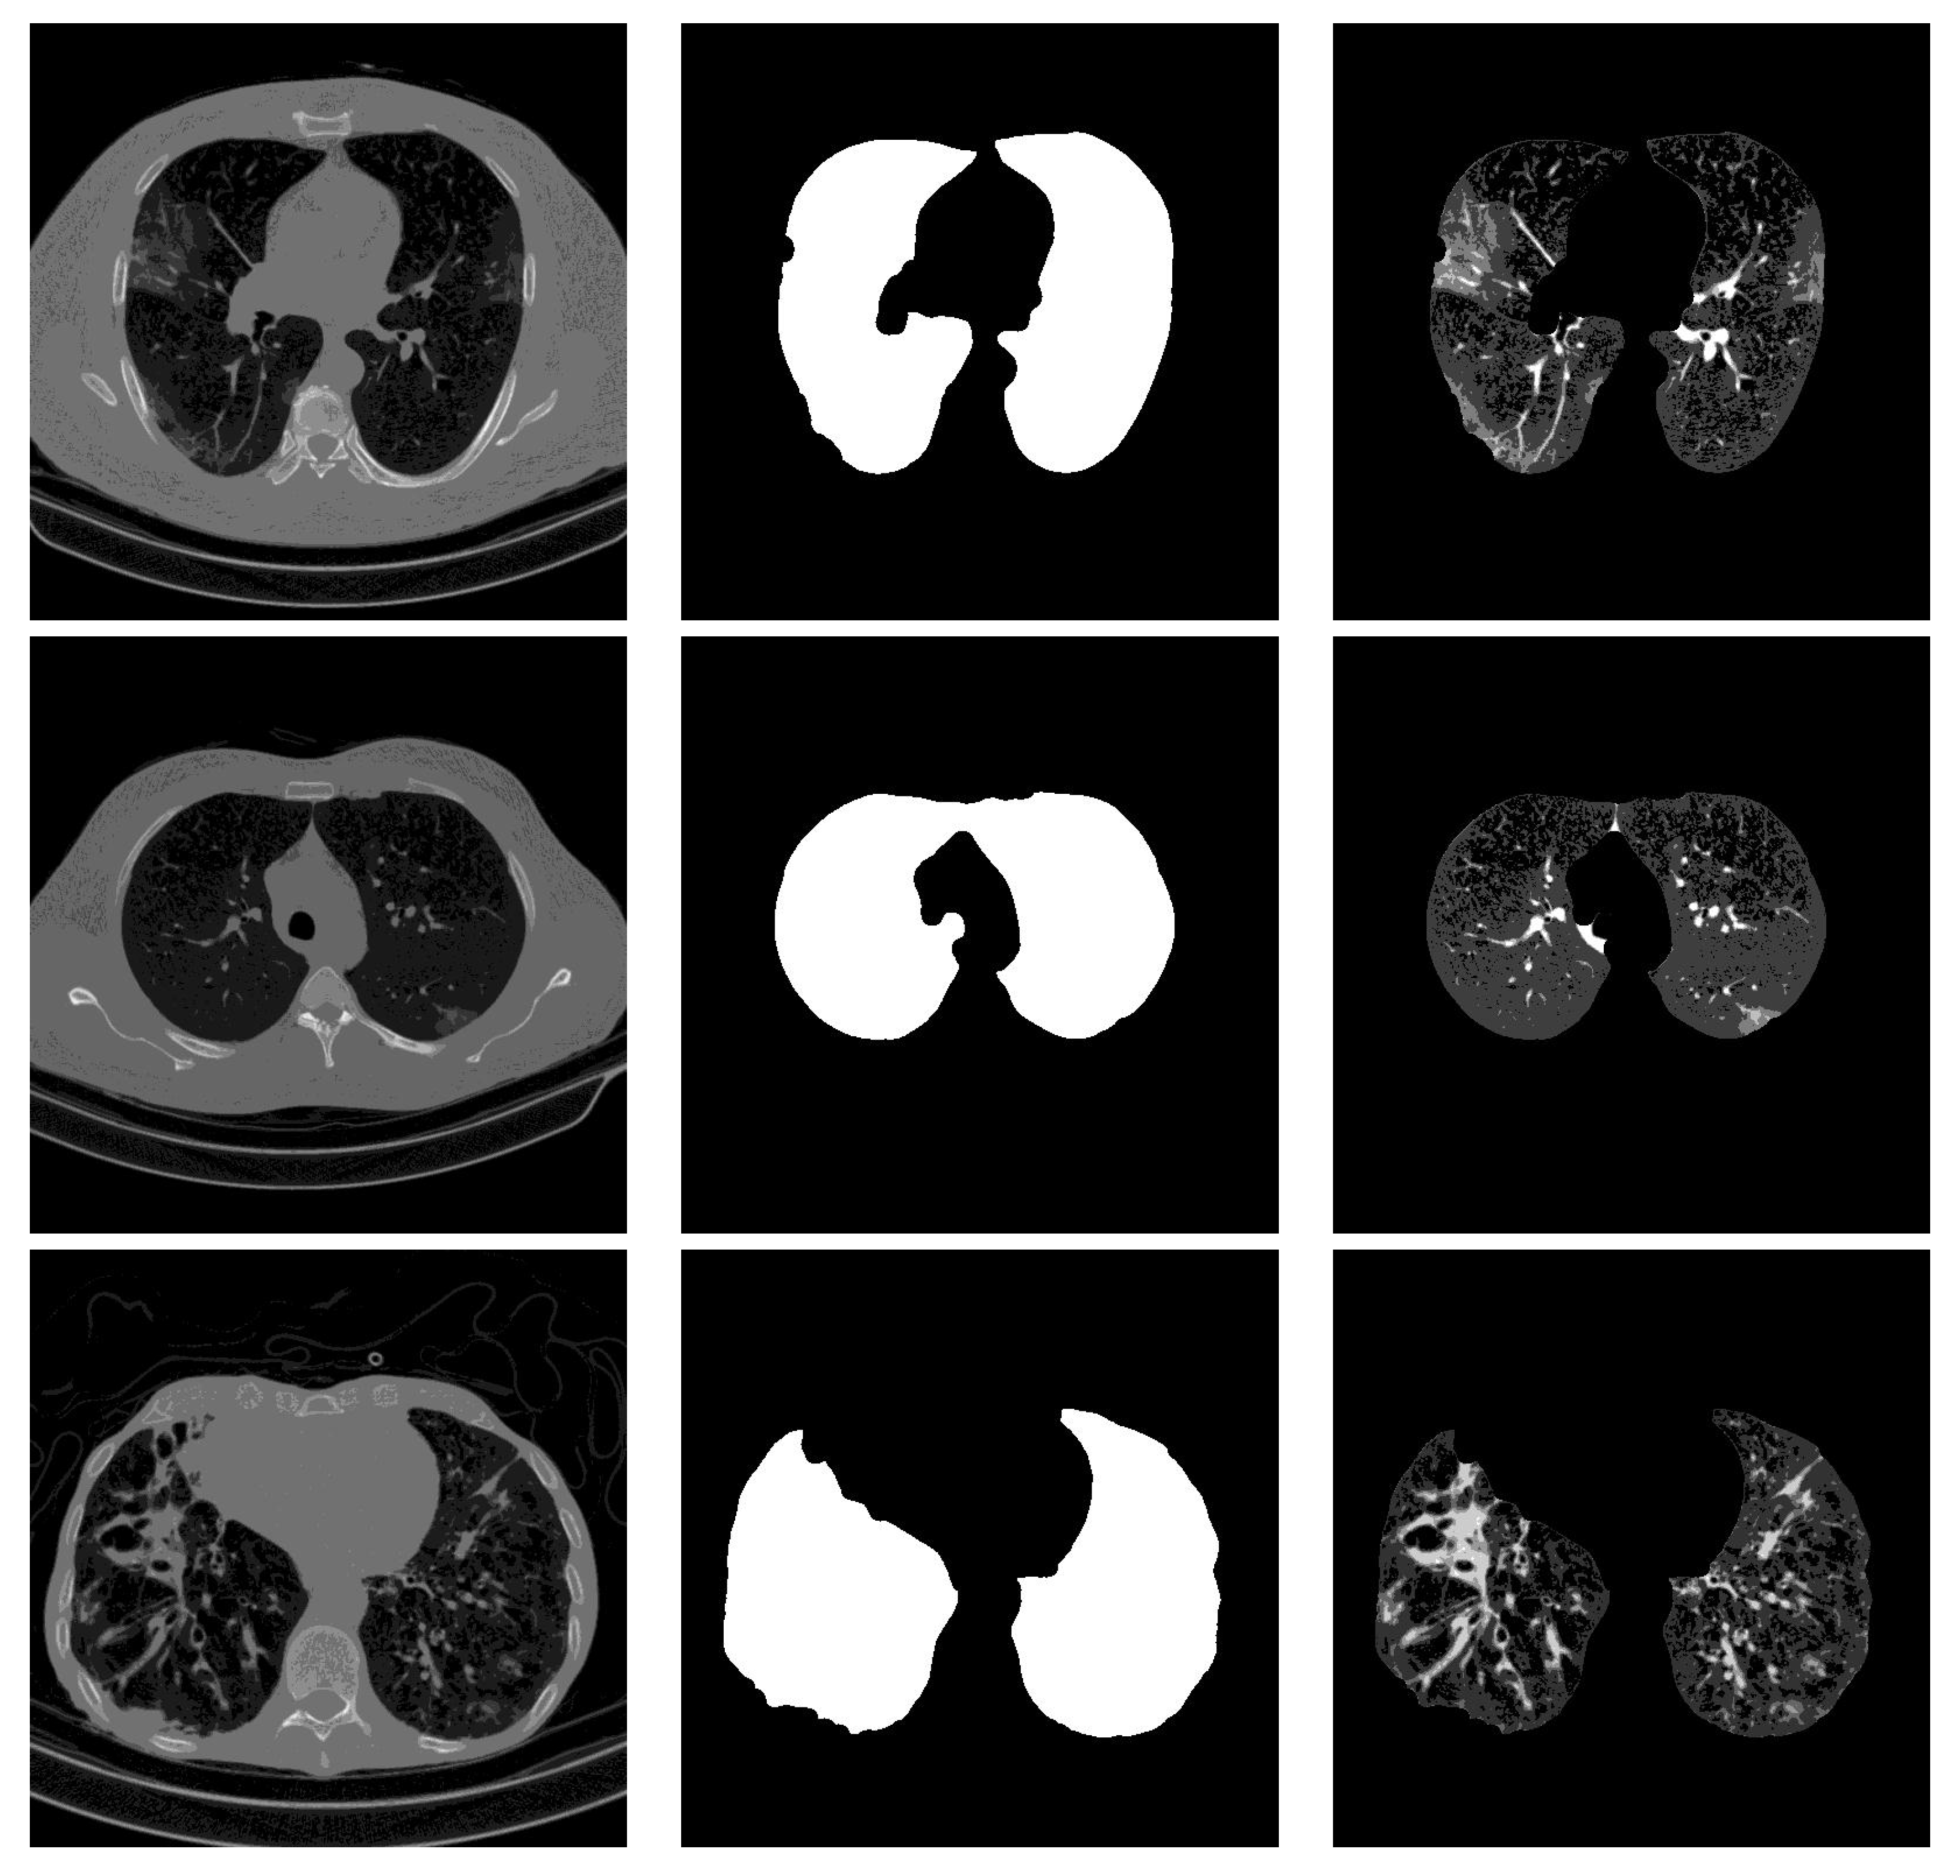

4.4. Segmentation Influence

Stacking segmented lung lobes with the grayscale image proved its efficiency (by comparing the results of Table 1 and Table 2). Despite this considerable improvement, the recognition of Cap slices needs more improvement. Figure 12 shows some segmented slices for COVID-19 and Cap cases. From Figure 12, we notice that the segmented results considered infection parts as lung lobes especially for Cap slices (row 2 and 3 Figure 12). One possible way to improve the performance of our approach is to use a CNN-based approach that were trained on infected slices to segment the lung lobes.

Figure 12.

Segmented lung lobes of infected slices with COVID-19 and Cap. Rows 1, 2, and 3 are for COVID-19, Cap, and Cap slices, respectively.